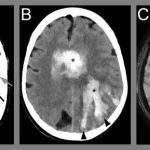

One of the most exciting facets of Aurora’s evolving healthcare scene is the application of AI in diagnostic imaging. Collaborative projects, such as the partnership between Advocate Health and Aidoc, have deployed the aiOS™ platform to significantly improve diagnostic accuracy across specialties like radiology, cardiology, neurovascular, and vascular care. By integrating a collection of FDA-cleared AI algorithms, clinicians can now pick up subtle abnormalities and diagnose conditions with a reported 94% accuracy rate compared to older techniques.

Advancements in technology have provided Aurora’s healthcare institutions with tools that upgrade patient care to a new level. AI-enhanced imaging devices allow for quicker detection of conditions like rib fractures and cervical spine injuries. Additionally, AI solutions support optimized radiation dosing in imaging procedures, thereby significantly reducing patient exposure while maintaining diagnostic precision.

In many cases, the goal is to reduce those overwhelming challenges associated with long wait times and the potential for diagnostic errors. AI deployments in radiology have been particularly beneficial; the technology helps identify anomalies that might otherwise be missed even by experienced professionals. Additionally, the use of AI to optimize radiation dosing not only makes the diagnostic process more efficient but also lessens the risk posed to patients by reducing unnecessary exposure to high levels of radiation.